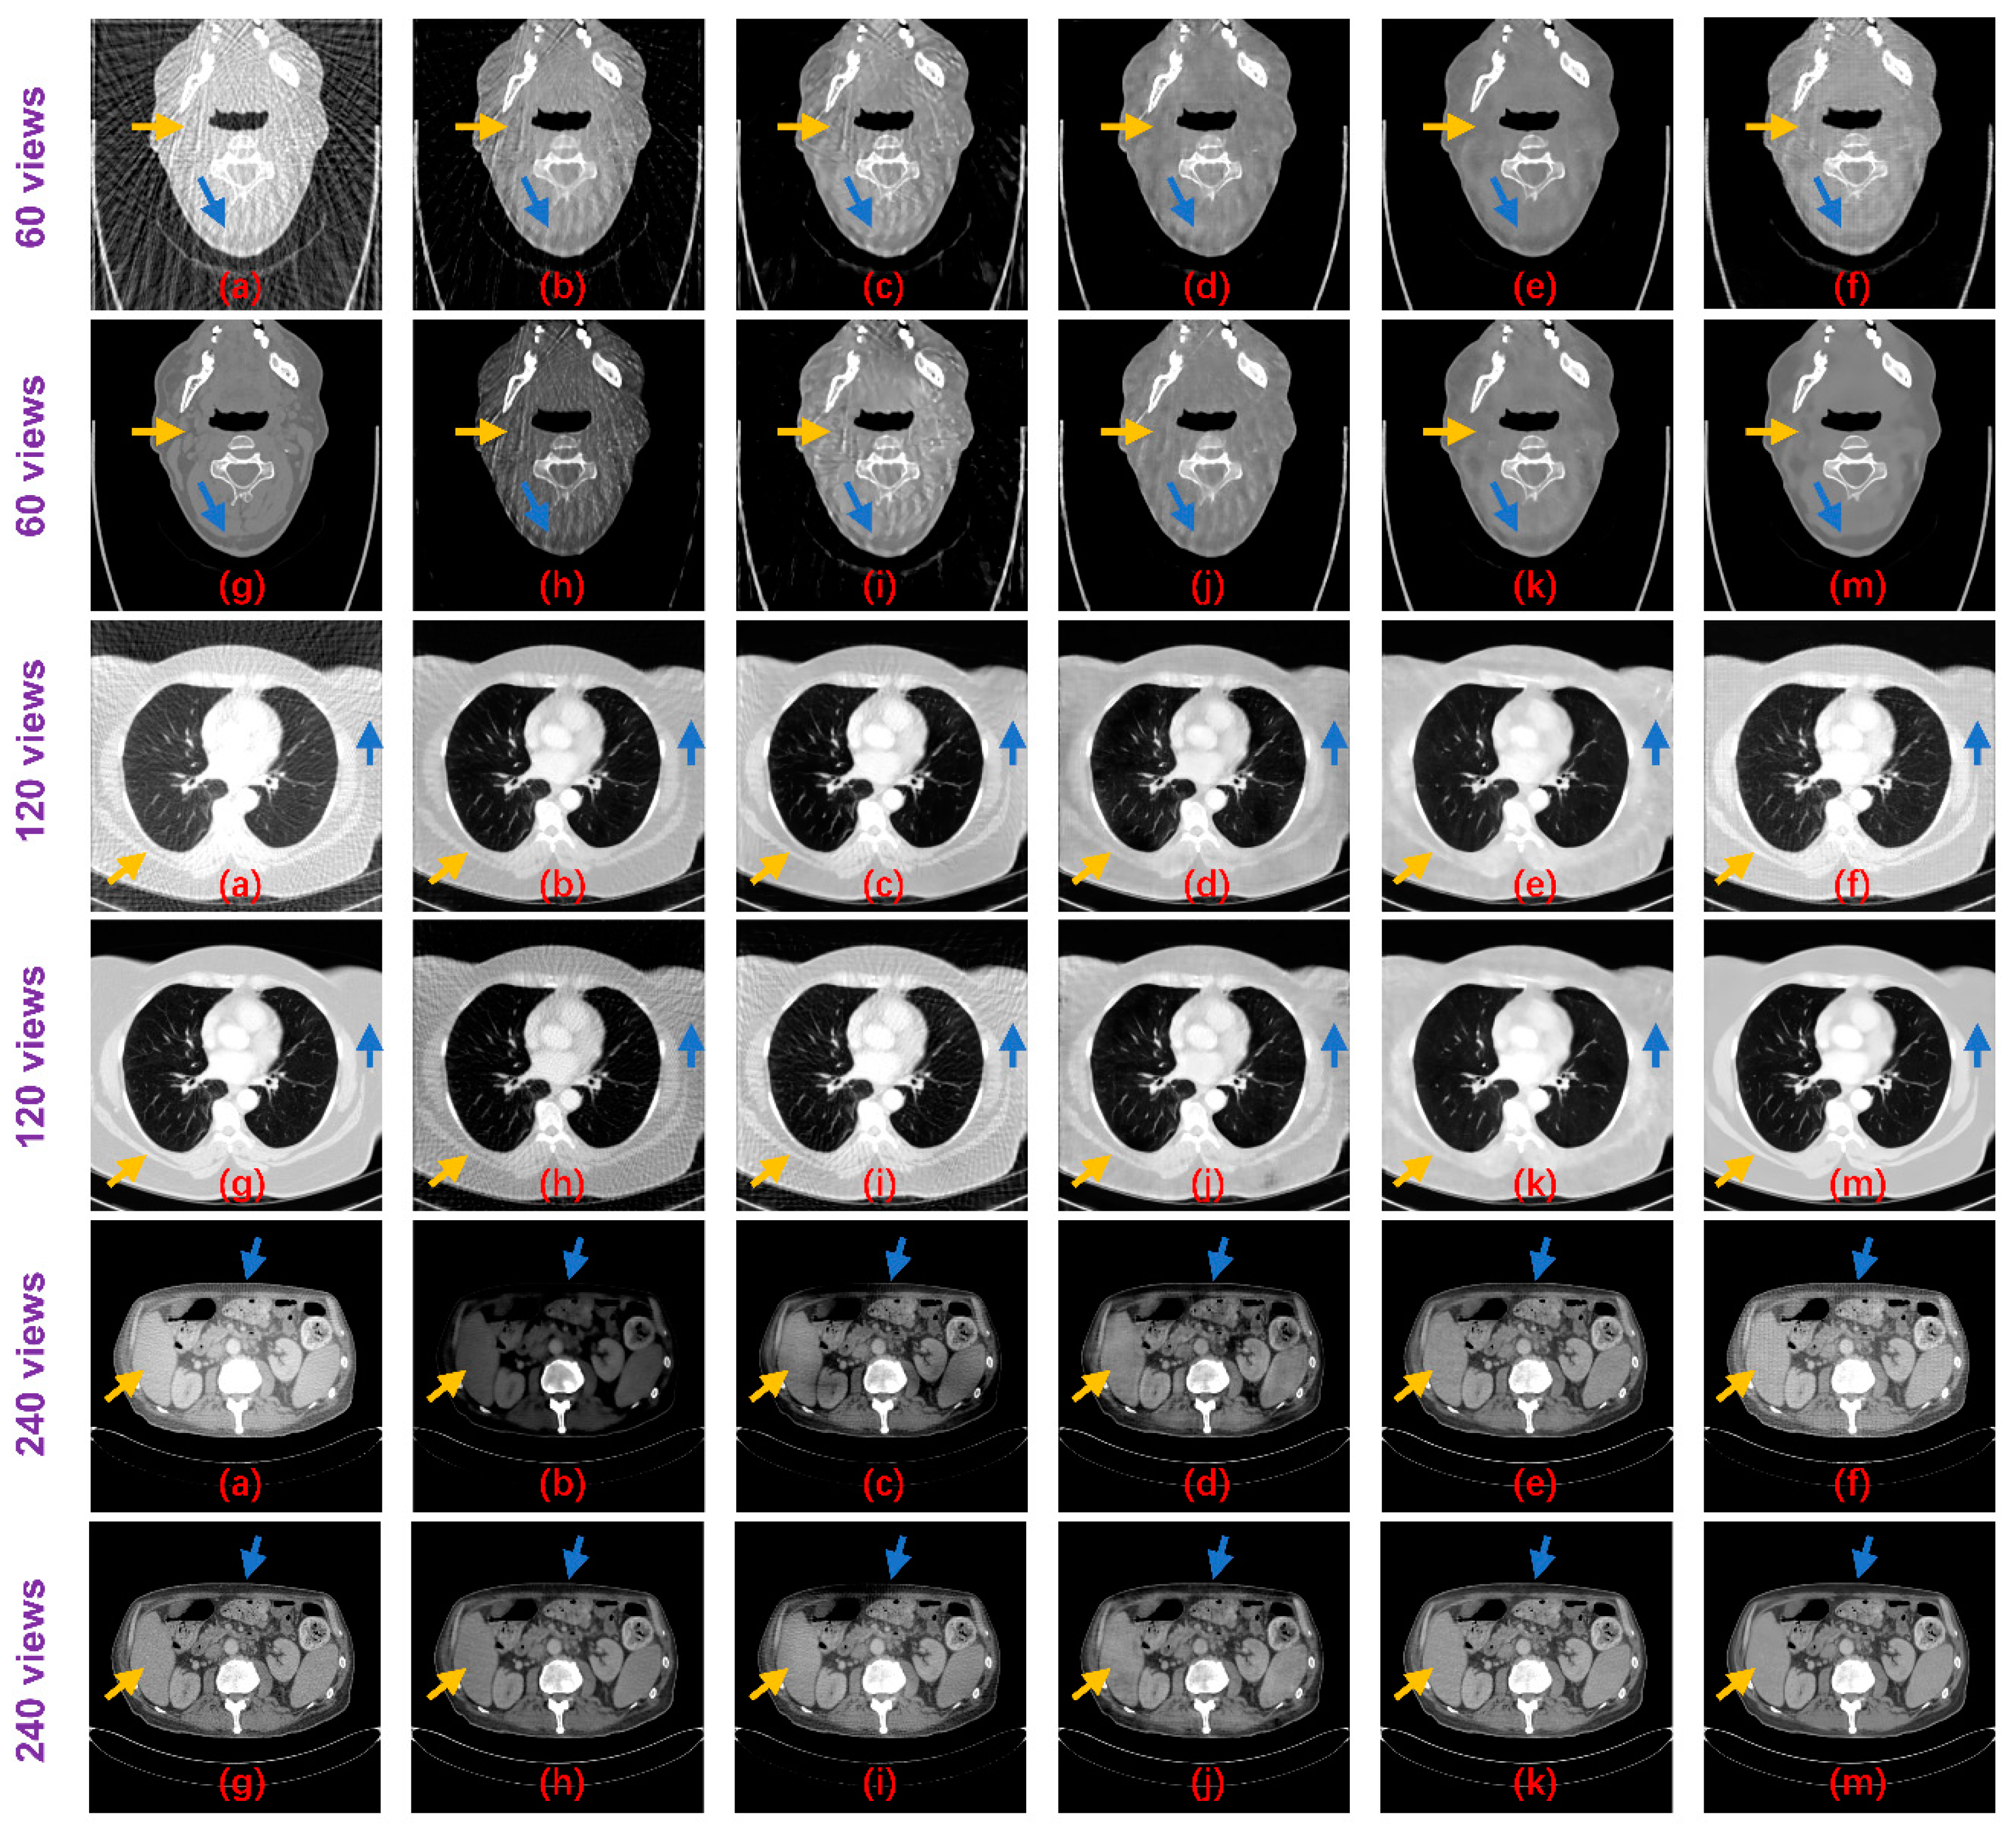

Table 2 shows the PSNR and SSIM results of these methods on the test datasets. Both non-deep learning methods performed worse than the deep learning methods, while for the deep learning algorithms, the Tight frame U-Net achieves higher PSNR and SSIM performance compared to Improved GoogLeNet with 25 times the number of parameters. The RED-CNN achieves better PSNR performance than the Tight frame U-Net, especially on the 60 views dataset and the network parameters are only 6% of the Tight frame U-Net, which we believe may be overfitted. Thanks to DenseNet and deconvolution’s ability to capture deep features of images, DD-NET obtains a better PSNR performance than RED-CNN, especially on the head and abdomen datasets, and higher SSIM, especially on the head and esophagus datasets. Particularly, our method outperforms all methods by achieving optimal PSNR and SSIM performance on all datasets. From the perspective of the degradation level, the PSNR of our method is on average 0.84 dB, 0.89 dB and 1.22 dB higher than DD-Net, respectively, for the 60 views, 120 views and 240 views datasets, and the SSIM results are on average 0.02, 0.01 and 0.01 higher, respectively. In terms of the body part, the PSNRs of our method are 0.89 dB, 0.94 dB, 1.29 dB and 0.80 dB higher than those of DD-Net for the head, abdomen, lung and esophagus, respectively, and the SSIM results are 0.02, 0.01, 0.02 and 0.01 higher, respectively. Figure 8 shows the reconstruction results of these methods. It can be seen that the artifact removal performance and detailed retention performance of our proposed method are optimal for all kinds of sparse-view datasets.

Figure 8.

Result images of the proposed method and the compared algorithms (blue and yellow arrows point out the detailed structural differences); (a) FBP; (b) Improved GoogLeNet; (c) Tight frame U-Net; (d) RED-CNN; (e) DD-Net; (f) frequency-domain module (FDM); (g) ground truth; (h) improved GoogLeNet+; (i) tight frame U-Net+; (j) RED-CNN+; (k) DD-Net+; and (m) ours.

For the networks that contain three sets of parameters corresponding to different degradation levels, Improved GoogLeNet+ has a PSNR advantage over Improved GoogLeNet on 60 views and 120 views while SSIM has an advantage only on 60 views. The performance of Tight Frame U-NET+ is generally weaker than that of Tight Frame U-NET, which may be due to the fact that the training dataset of Tight Frame U-NET+ only targets one degradation level, while the training set of Tight Frame U-NET contains three types of degradation, which moderates the overfitting problem to some extent. The average performance of Red-CNN+ and DD-NET+ is better than that of Red-CNN and DD-NET, but still worse than that of our model and more parameters are used. The standard deviations of PSNR and SSIM for our method on the test dataset are shown in Table 3. Suppose the PSNR and SSIM results are both independent samples from a normally distributed population, Table 3 also displays the 95% confidence intervals for PSNR and SSIM results on the test dataset. Figure 9 displays the difference images between the result images and the ideal CT images. It can be seen that the proposed method can reduce the overall intensity error compared to other methods, therefore, achieves better visual performance.

With the explicit learning of degradation levels in both the frequency and image domain, our method outperforms all the deep learning-based methods in terms of different degradation levels and body parts, as well as achieves a satisfactory trade-off between the size of the network and the performance (Table 1). Moreover, the statistical significance of the testing results (Table 4 and Figure 10) demonstrates that the differences in the PSNR and SSIM results between the proposed method and other methods are statistically significant. In addition, our method achieves better visual results with more textual structure details and less reconstruction error (Figure 8 and Figure 9).